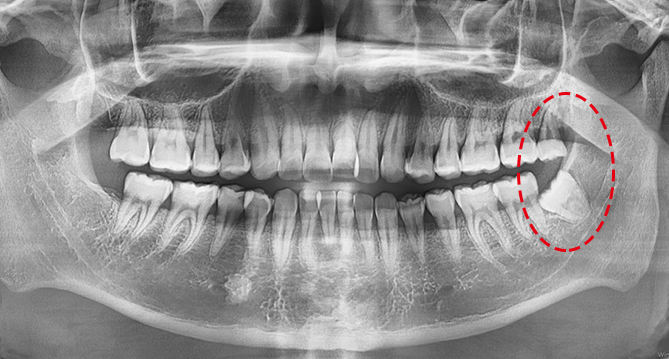

오차없는 진단시스템, 3D CT

최첨단 3D CT를 통해 맞춤형 임플란트 수술이 가능하며

누워계신 상태로 편안하고 간편하게 방사선 촬영이 가능한

최신형 이동형 엑스레이도 사용하고 있습니다.